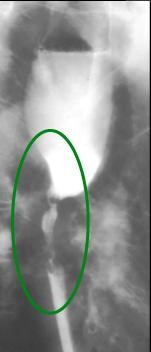

Carcinome epidermoide

:Forme ulcero bourgeonnante etendue . La lesion

depasse 5cm |